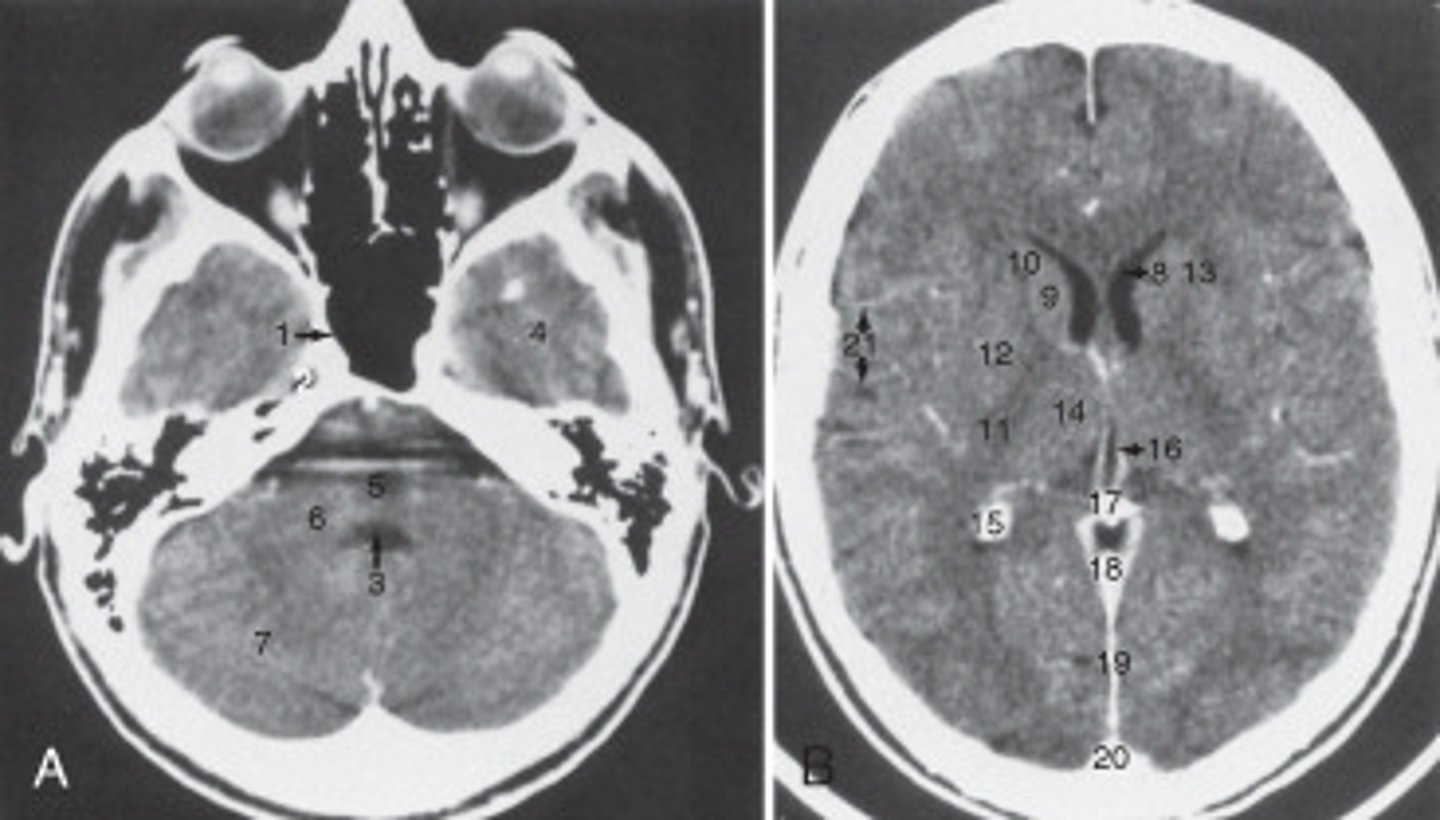

The anterior (frontal) horn of the lateral ventricle is labeled as:

<p>The anterior (frontal) horn of the lateral ventricle is labeled as:</p>

The thalamus is labeled:

<p>The thalamus is labeled:</p>

the fall cerebri is labeled:

<p>the fall cerebri is labeled:</p>

The structure labeled 15 is the:

<p>The structure labeled 15 is the:</p>

The structure labeled 3 is the:

<p>The structure labeled 3 is the:</p>

The internal jugular vein is labeled:

<p>The internal jugular vein is labeled:</p>

the parotid gland is labeled:

<p>the parotid gland is labeled:</p>

the structure labeled as 8 is the:

<p>the structure labeled as 8 is the:</p>